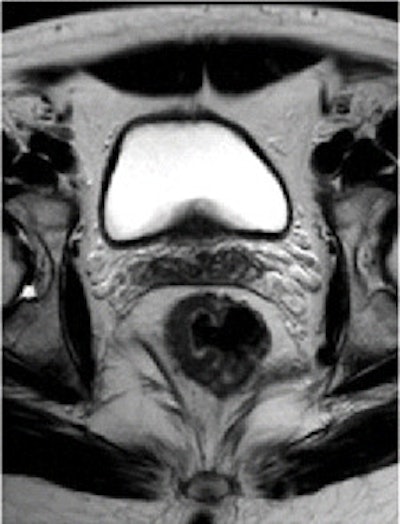

Pre- and post-treatment MRI was performed with a 1.5-tesla system (Intera R10, Philips Healthcare) using an eight-element pelvic phased-array surface coil. The subjects were imaged in the prone position after the placement of a thin rectal catheter in the rectum.

After initial localization imaging, researchers acquired MR images of the pelvis and rectum, with T2-weighted images obtained in the transverse, coronal, and sagittal planes during the scanning time of approximately 30 minutes.

Two radiologists, who were blinded to clinical information about each patient, independently evaluated the images obtained before and after chemotherapy and radiation treatment.

The MR images calculated the mean tumor volume was 58 cm3 ± 75 before chemotherapy/radiation treatment and 20 cm3 ± 31 after therapy. The mean tumor volume reduction ratio in all patients was 68% ± 23.